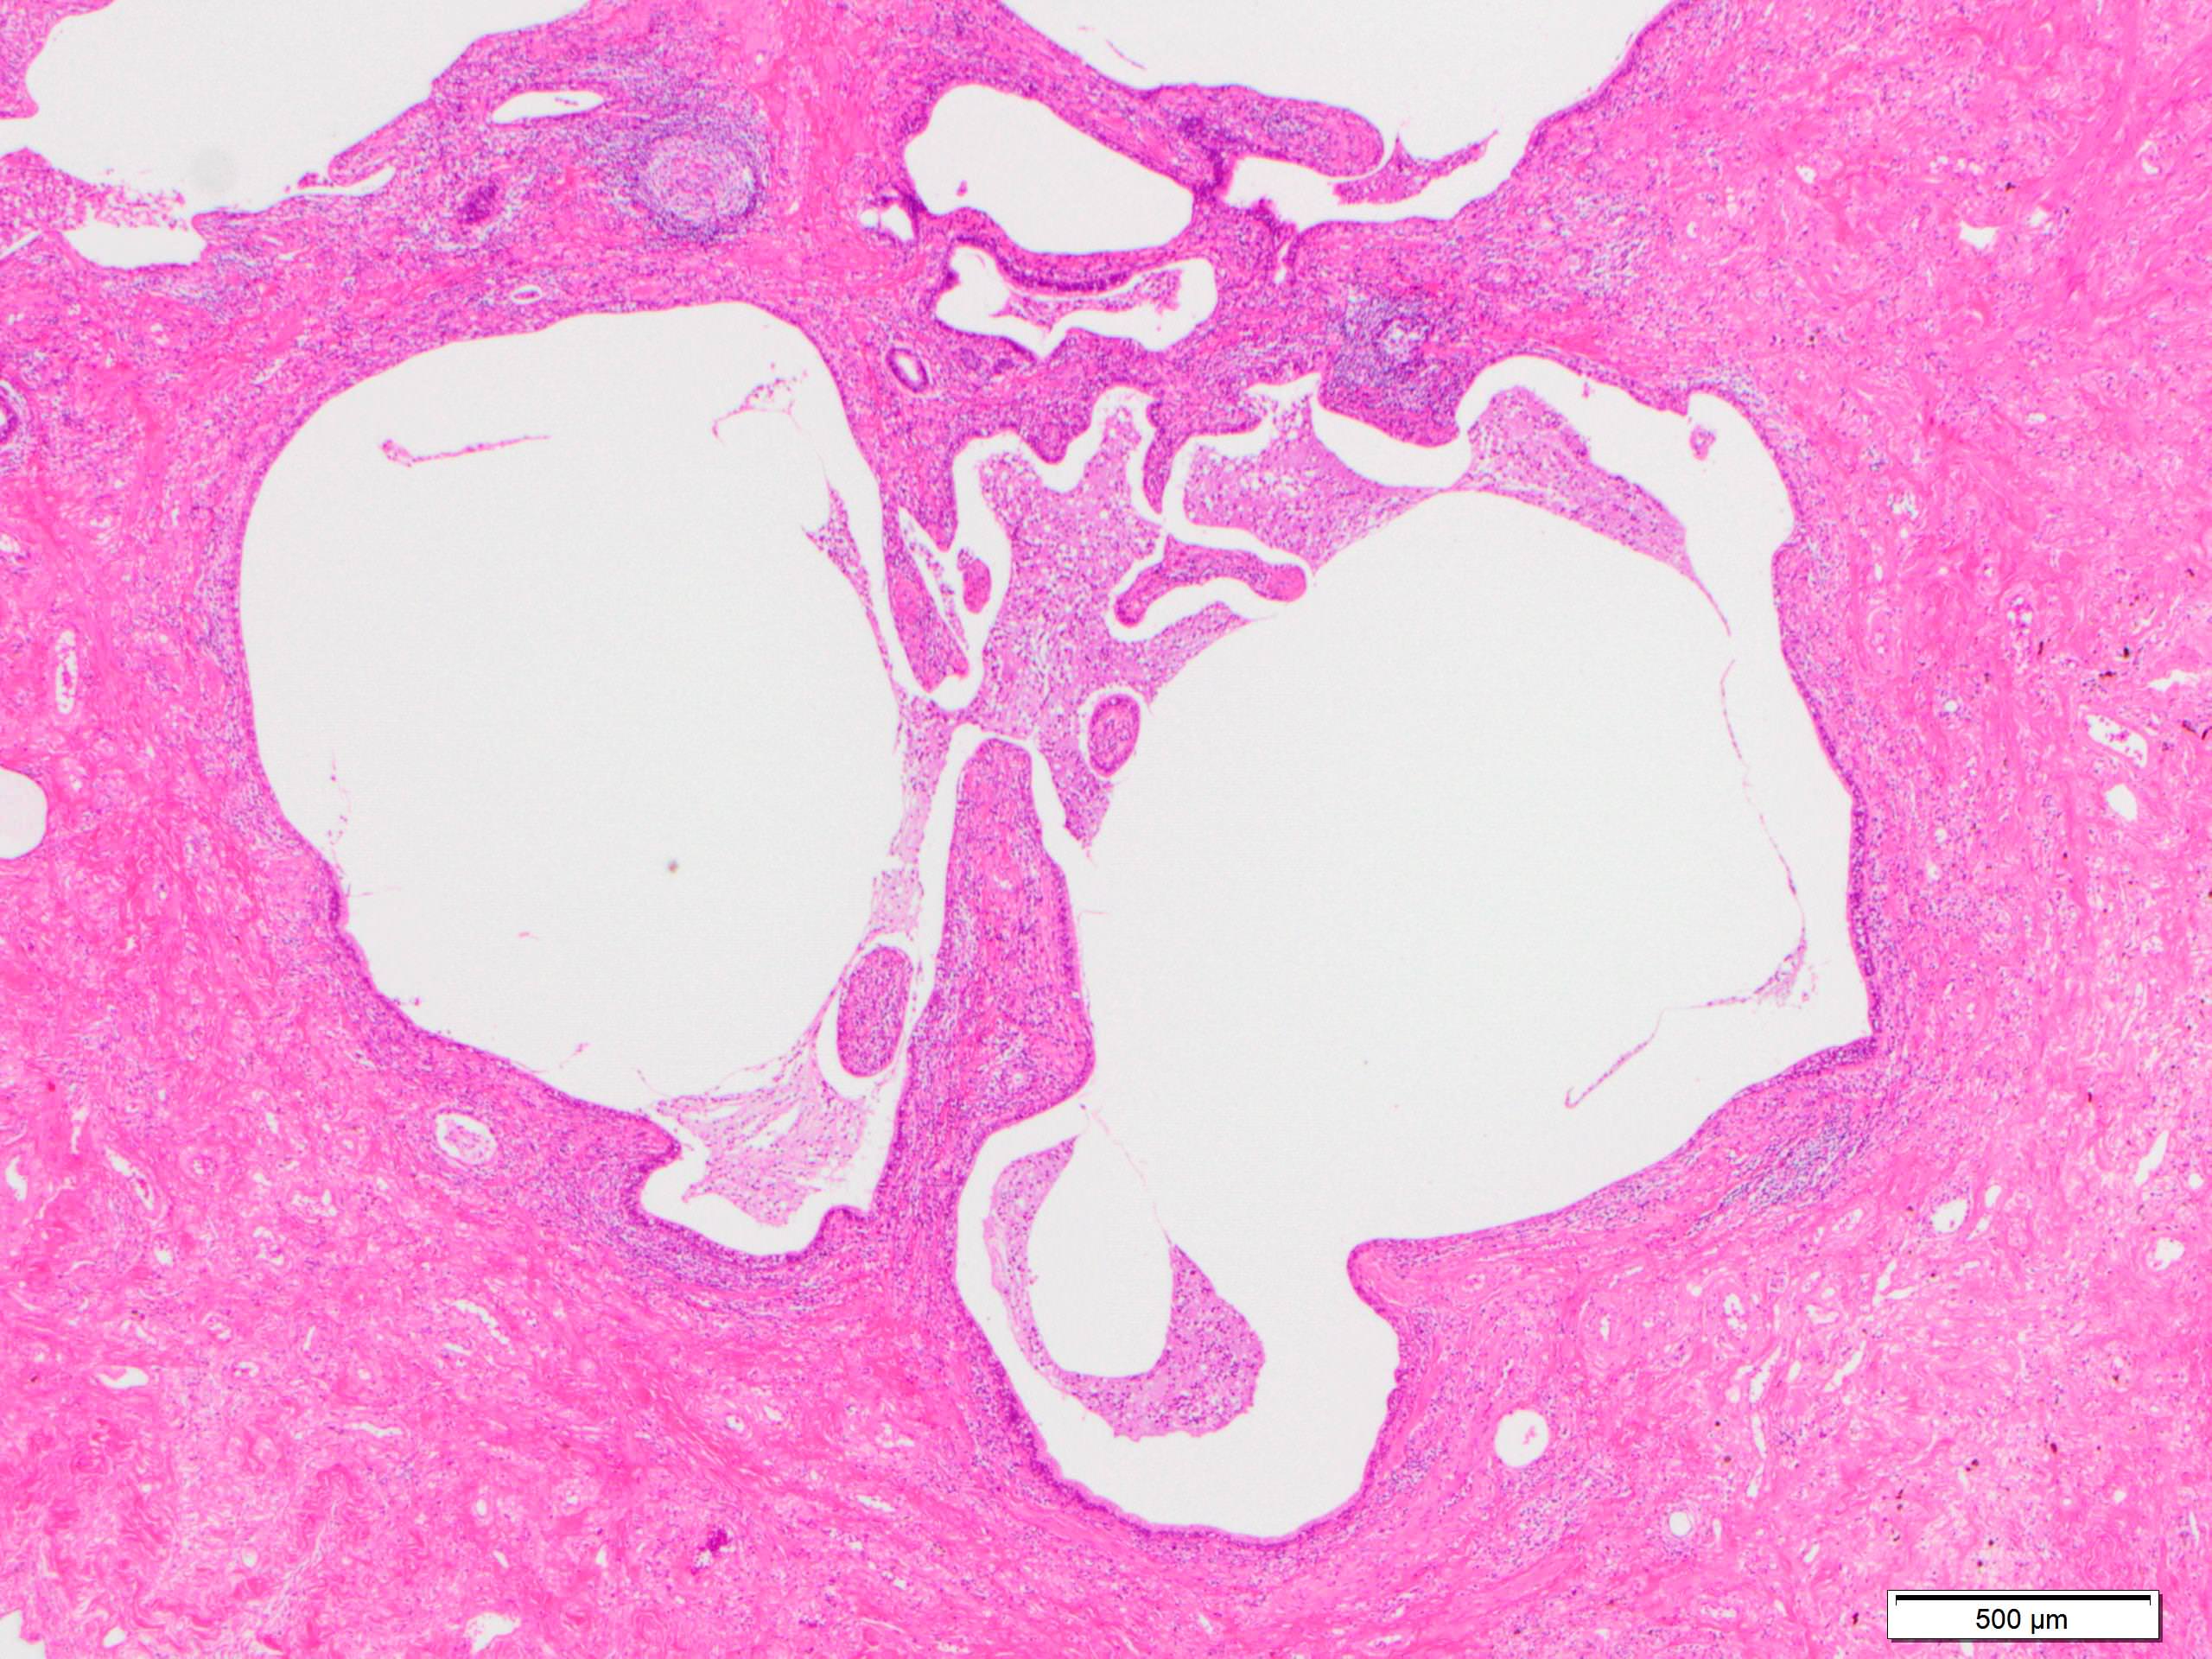

Microscopic (histologic) description

- Since there are few specific findings for NSIP pattern, it is essential to exclude other lung diseases on histology (Am J Respir Crit Care Med 2008;177:1338)

- Characteristic findings of NSIP pattern

- Diffuse and uniform inflammation ("temporal homogeneity") on low power of alveolar wall, bronchovascular bundles and pleura

- Cellular or fibrotic change

- Loose fibrosis

- Lung architecture is frequently preserved

- "Cellular NSIP" or "fibrotic NSIP" can be stated specifically in pathologist report

- Pertinent negative findings (Am J Respir Crit Care Med 2008;177:1338)

- UIP-like change

- Marked architectural distortion

- Dense fibrosis with smooth muscle hyperplasia or elastosis

- Fibroblastic foci

- Honeycomb change

Microscopic (histologic) images

Scroll to see all images.

Contributed by Akira Yoshikawa, M.D.

Images hosted on other servers:

Contributed by Akira Yoshikawa, M.D.

Images hosted on other servers: